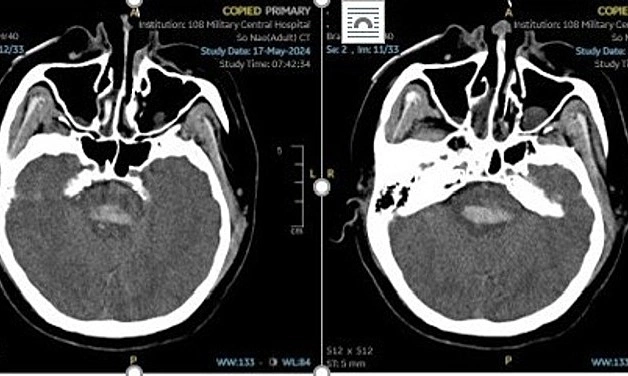

Tương tự, bác sĩ Nguyễn Tiến Dũng, Phó Giám đốc Trung tâm Đột quỵ, Bệnh viện Bạch Mai, từng tiếp nhận người đàn ông 30 tuổi, chủ quan không kiểm soát huyết áp tốt, phải nhập viện hai lần, khi đến viện đã hôn mê, phải đặt ống nội khí quản và huyết áp liên tục tăng cao 180/100 mmHg. Chỉ số huyết áp không giảm ngay cả khi đã được sử dụng thuốc truyền tĩnh mạch.

Bệnh nhân có tiền sử chảy máu não do tăng huyết áp 4 năm trước. Khi điều trị ổn định, anh được cho về nhà dùng thuốc để điều trị tăng huyết áp. Sau một thời gian, bệnh nhân thấy huyết áp bình thường, chủ quan nghĩ rằng bệnh đã khỏi nên tự ý bỏ thuốc.

Bác sĩ nói khó có thể làm phẫu thuật do người bệnh đã chảy máu cả hai bên não và hôn mê sâu, được chỉ định tiếp tục điều trị hồi sức nội khoa, tiên lượng nặng.